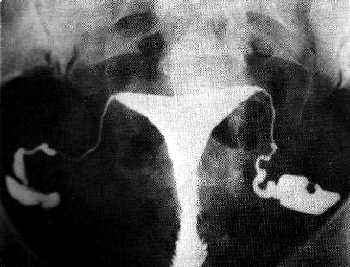

Szóval a lényeg: cisztát nem látott, levette a rákszűrést, azt mondta, nincs semmi látható baj, úgyhogy teherbe kell esnem.

Felírt ő is clostyt, de most nem tudom, hogy szerintetek el merjem kezdeni szedni megint, hogy a múltkor ciszta lett tőle? Na és ha két hónapig szedem és nem leszek terhes, akkor inszemináció. Ez annyira borzasztó, hogy idáig jutottam, de ugyanakkor örülök is neki, hogy végre legalább van valami terv, ami mentén haladunk, nemcsak visszajárogatok a nagy semmire.